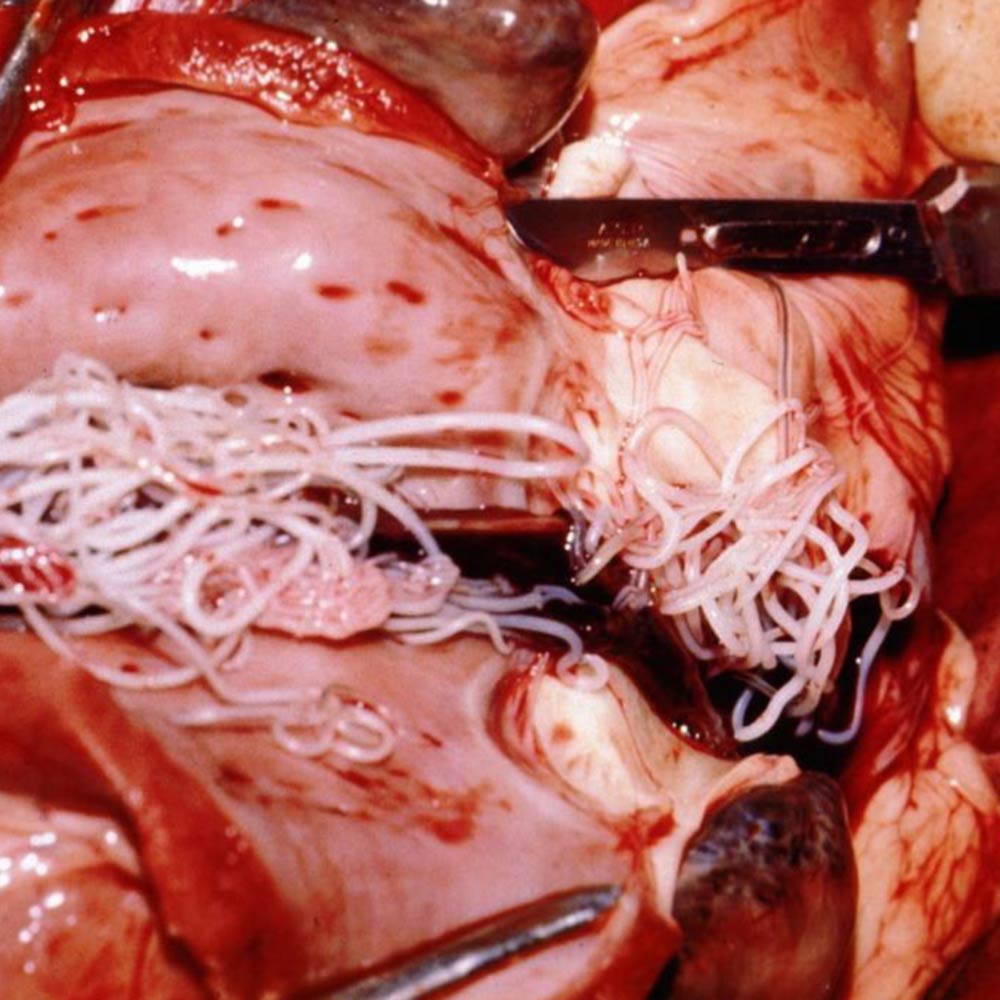

Möglicher Parasitenbefall